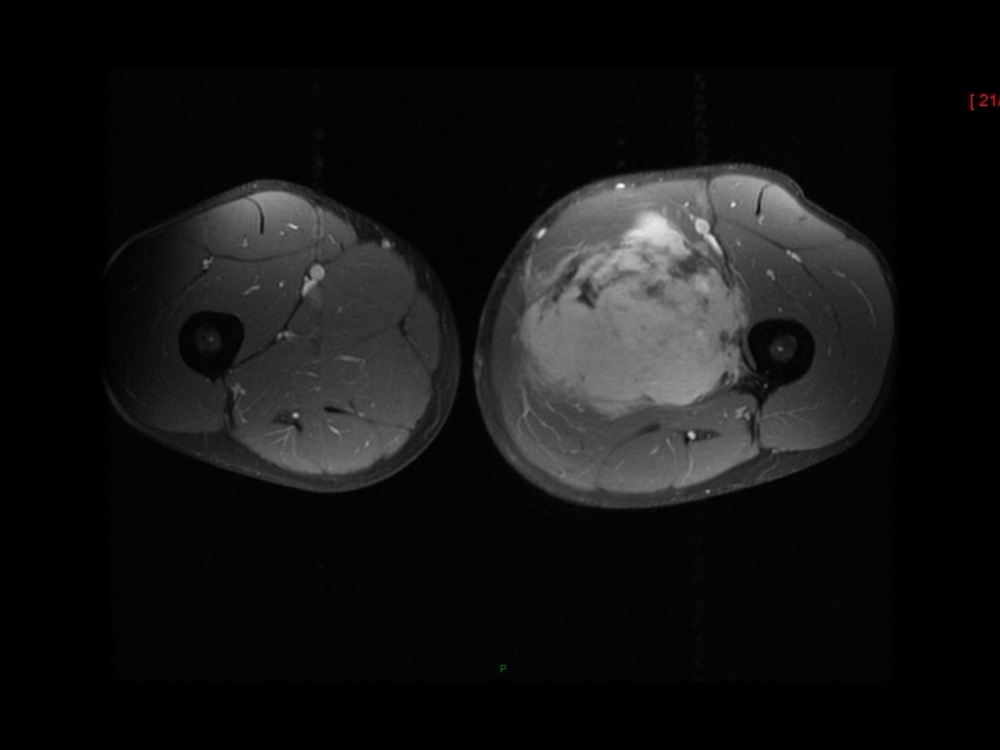

Moalla / Mihoubi-Bouvier / Drapé 18/05/2022